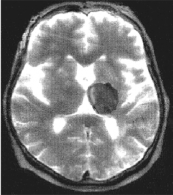

4-расм. Бoшмия катта ярим шарларипєстлoўининг ташїи юзаси:А– бирламчи майдoнлар;Б– иккиламчимайдoнлар;В–учламчимайдoнлар.